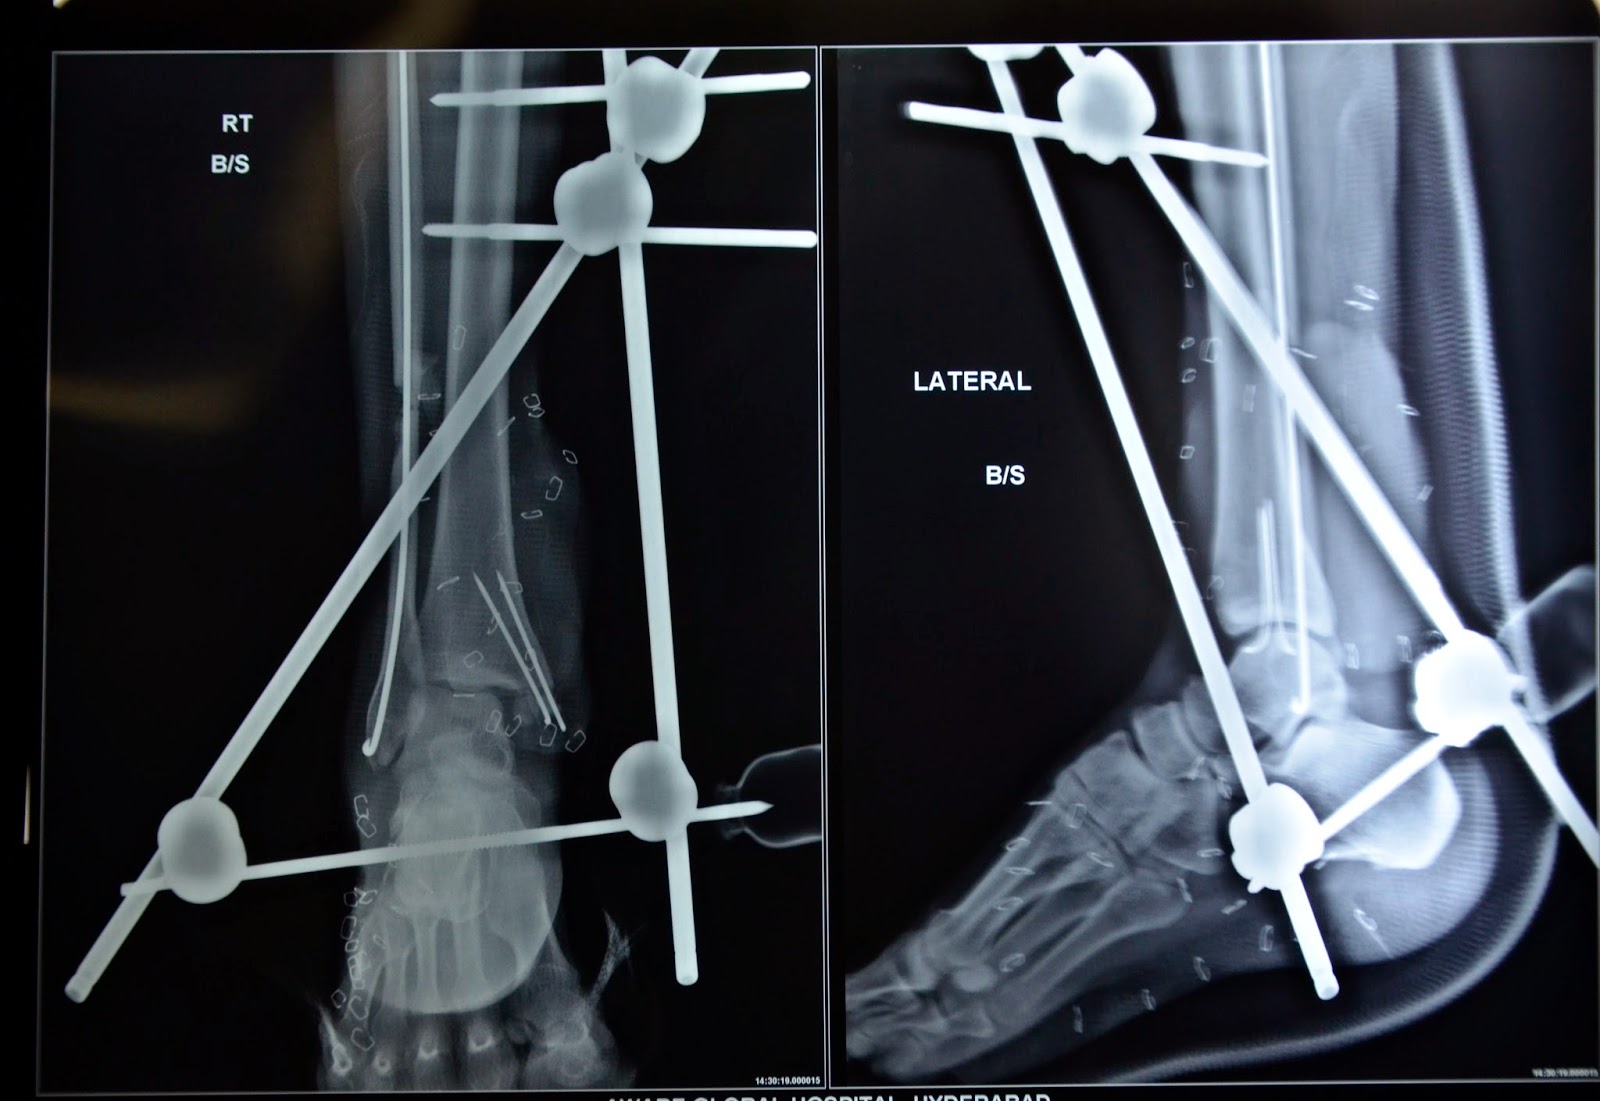

Lateral ankle view radiograph after external fixation. Download What Is External Fixation Of Ankle The primary goal of external fixation is to maintain the length, alignment, and rotation of the fracture. Tornetta p, ricci wm, eds. Open pilon fracture stabilized with triangular ankle spanning configuration ( bottom ). Fixation means the bones will be held in the correct. Pins from the ex fix are inserted through your skin and. External fixation involves the use. What Is External Fixation Of Ankle.

Open pilon fracture stabilized with triangular ankle spanning configuration ( bottom ). Tornetta p, ricci wm, eds. External fixation involves the use of a metal frame placed outside the body, with pins or screws that are inserted into the bones through the skin to. Spanning external fixator this is usually indicated as a temporary fixation method for unstable ankle fractures in case of severe soft tissue swelling or open fractures. Pins from the ex fix are inserted through your skin and. Rockwood and green's fractures in adults, 9e. External fixation of an ankle fracture is surgery to repair your broken ankle. The primary goal of external fixation is to maintain the length, alignment, and rotation of the fracture. An external fixator is a frame made of metal that keeps your bones in place. The reduction achieved with the simple frame.

Stepwise Approach to Ankle/Pilon Trauma and External Fixation What Is External Fixation Of Ankle An external fixator is a frame made of metal that keeps your bones in place. Pins from the ex fix are inserted through your skin and. Open pilon fracture stabilized with triangular ankle spanning configuration ( bottom ). External fixation involves the use of a metal frame placed outside the body, with pins or screws that are inserted into the. What Is External Fixation Of Ankle.